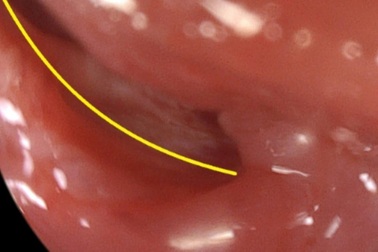

Cẩn trọng: Dị vật thực quản do ung thư thực quảnỞ giai đoạn muộn, khối u thực quản lan rộng gây ra nhiều phiền toái cho người bệnh. Biến chứng hay gặp là tắc thực quản do u chèn ép hoàn toàn khẩu kính của thực quản.

Ho nặng kéo dài có thể do rối loạn vận động thực quảnRối loạn vận động thực quản - vấn đề chiếm 90% ca bệnh thực quản thường bị bỏ sót, điều trị không hiệu quả - có thể được chẩn đoán chính xác với 2 kỹ thuật mới là đo vận động thực quản độ phân giải cao (HRM) và đo pH trở kháng thực quản 24h.

U thực quản lành tính điều trị như thế nào?U cơ trơn thực quản là khối u lành tính ở thực quản, đây là tổn thương hiếm gặp, chiếm tỷ lệ nhỏ (< 1% các khối u thực quản).

Dấu hiệu sớm của ung thư thực quảnUng thư thực quản là khối u ác tính xuất phát từ các tế bào biểu mô của thực quản. Bao gồm hai loại chính là ung thư biểu mô vảy và ung thư biểu mô tuyến.